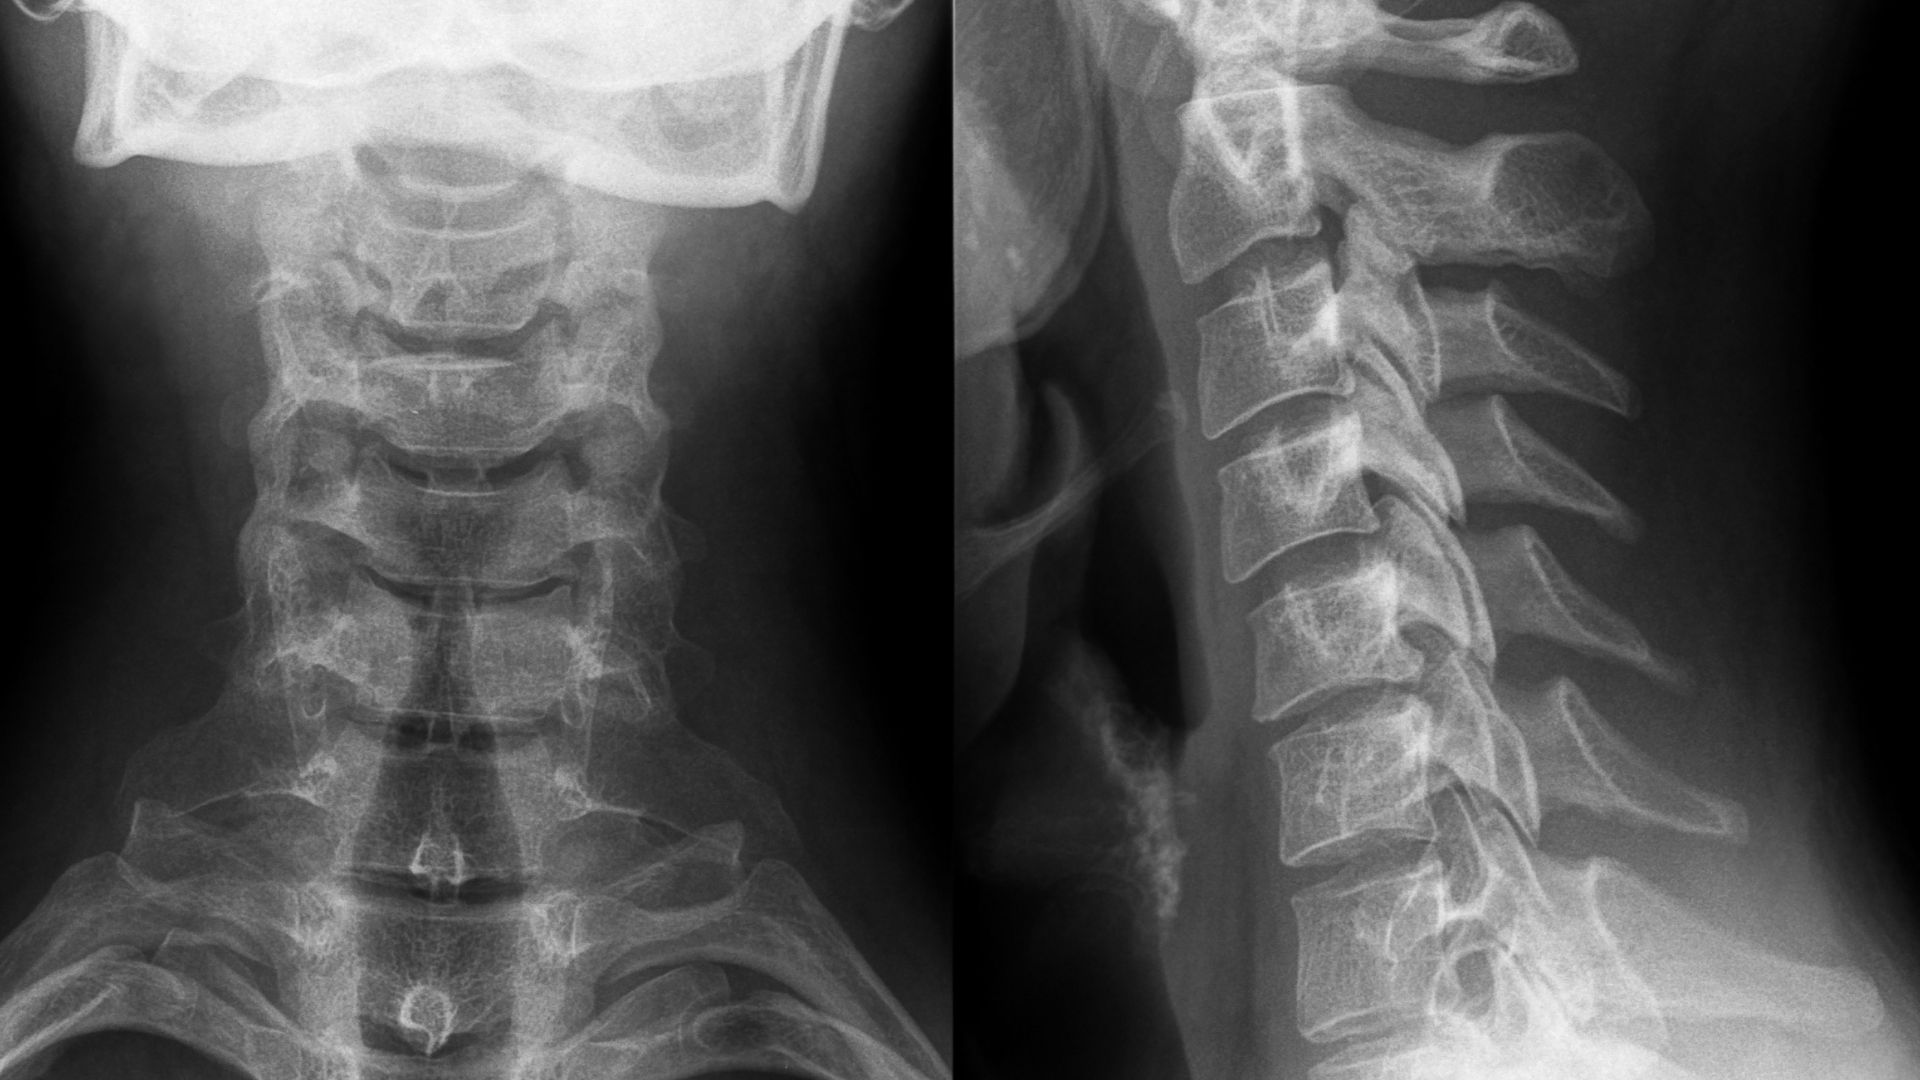

X-quang cột sống cổ là kỹ thuật chẩn đoán hình ảnh sử dụng tia X để tạo ra hình ảnh cấu trúc xương và các thành phần liên quan ở vùng cổ. Phương pháp này chiếu tia X qua cơ thể, với xương hấp thụ nhiều tia hơn nên hiện lên màu trắng trên phim, trong khi mô mềm hiện màu xám đen. Kỹ thuật khảo sát chủ yếu 7 đốt sống cổ từ C1 đến C7, bao gồm thân đốt sống, khe đĩa đệm, mỏm gai, mỏm ngang và đường cong sinh lý ưỡn ra trước của cột sống cổ.

Quy trình chụp X-quang cột sống cổ diễn ra nhanh chóng, thường chỉ mất vài phút và không xâm lấn. Các tư thế chụp thường gặp bao gồm:

- Tư thế thẳng (AP): Người bệnh đứng hoặc ngồi, mặt quay về phía nguồn tia X, hai tay xuôi dọc cơ thể, cằm hơi ngửa để vùng gáy sát phim.

- Tư thế nghiêng (lateral): Người bệnh đứng hoặc ngồi chếch, vai và gáy sát phim, cằm ngửa nhẹ để đường cong cột sống cổ hiển thị rõ.

- Tư thế chếch (oblique, nếu cần): Để đánh giá thêm lỗ tiếp hợp hoặc các cấu trúc bên, thường chụp ở góc 45 độ.

X-quang cột sống cổ là phương pháp chẩn đoán hình ảnh cơ bản, thường được sử dụng đầu tiên khi người bệnh có triệu chứng đau cổ. Phương pháp này tập trung khảo sát cấu trúc xương, với ưu điểm là thực hiện nhanh, chi phí thấp và dễ tiếp cận tại hầu hết các cơ sở y tế. Nhờ X-quang, bác sĩ có thể quan sát hình dạng các đốt sống cổ, đường cong sinh lý và phát hiện sớm các bất thường rõ ràng về xương như gãy, trượt hoặc thoái hóa.